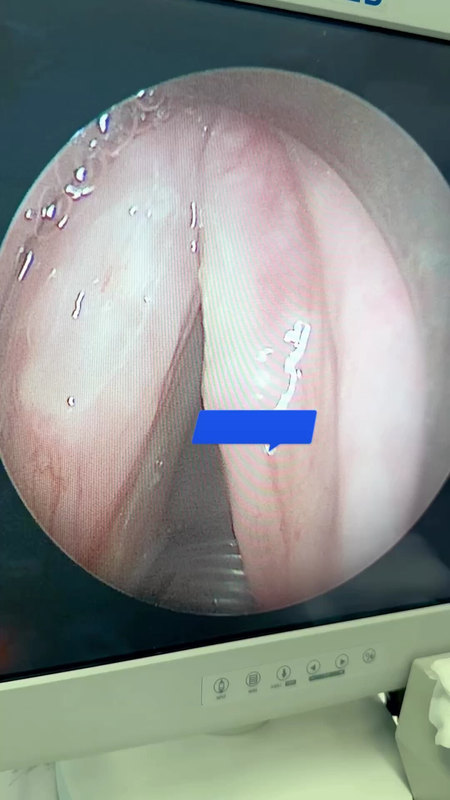

聲帶上的白斑是什么,這次徹底搞明白了

最近來自江西贛州的葉先生,53歲了。半年前咳嗽后出現(xiàn)咽部異物感,伴刺激性咳嗽,無伴聲嘶,咳嗽后發(fā)聲費力,無伴反酸、燒心感,無呼吸困難、吞咽障礙,在外院行喉鏡檢查提示“左側(cè)聲帶腫物”,藥物治療后效果一般,今為進一步診治。檢查后發(fā)現(xiàn)聲帶上有白斑,這種情況建議手術(shù)切除。入院后安排了全麻聲帶腫物切除術(shù),插管全麻后在內(nèi)鏡下切除聲帶的白色腫物,組織送病理檢查,發(fā)現(xiàn)是鱗狀上皮伴輕度不典型增生。這種情況一般需要戒煙、戒酒,防止病變繼續(xù)發(fā)展成為腫瘤。關(guān)于聲帶腫物,如果您還有什么問題,歡迎留言和耳鼻喉鄭立崗醫(yī)生進一步交流。